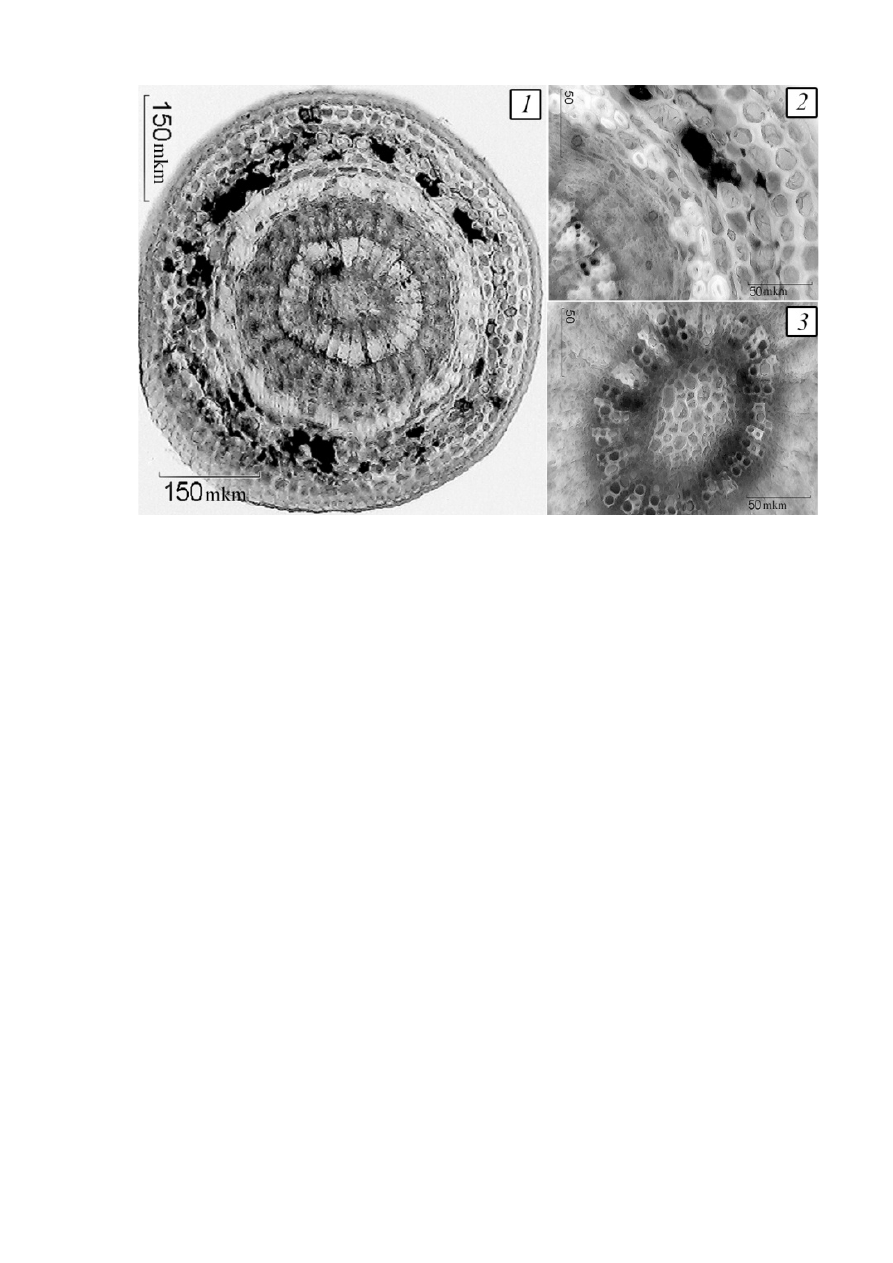

Рисунок

2–

Поперечный срез плодоножки жостера.

1 –

Общий вид плодоножки (

100×); 2 –

фрагмент коровой части с

пигментом и склеренхимой (

400×); 3 –

фрагмент сердцевины

плодоножки